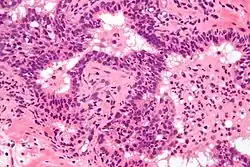

Acute prostatitis is relatively easy to diagnose due to its symptoms that suggest infection. The organism may be found in blood or urine, and sometimes in both.[2] Common bacteria are Escherichia coli, Klebsiella, Proteus, Pseudomonas, Enterobacter, Enterococcus, Serratia, and Staphylococcus aureus. This can be a medical emergency in some patients and hospitalization with intravenous antibiotics may be required. A complete blood count reveals increased white blood cells. Sepsis from prostatitis is very rare, but may occur in immunocompromised patients; high fever and malaise generally prompt blood cultures, which are often positive in sepsis. A prostate massage should never be done in a patient with suspected acute prostatitis, since it may induce sepsis. Since bacteria causing the prostatitis is easily recoverable from the urine, prostate massage is not required to make the diagnosis. Rectal palpation usually reveals an enlarged, exquisitely tender, swollen prostate gland, which is firm, warm, and, occasionally, irregular to the touch. C-reactive protein is elevated in most cases.[4]